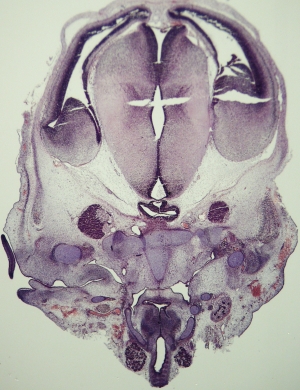

Stage 20

CfS 20

d35-38